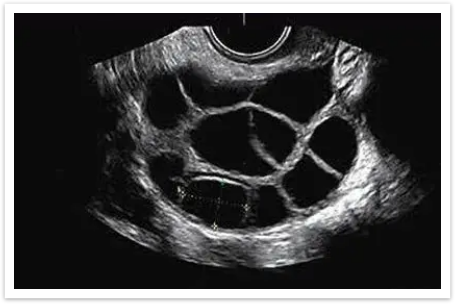

✅揪出「隐形问题」:有些情况肉眼无法察觉,比如卵泡长到一定程度却不破裂(未破裂卵泡黄素化综合征),或者卵泡没长够大小就提前排出。这些问题都会影响受孕,而动态监测能及时发现异常,为医生调整方案提供依据。

▲卵泡黄素化